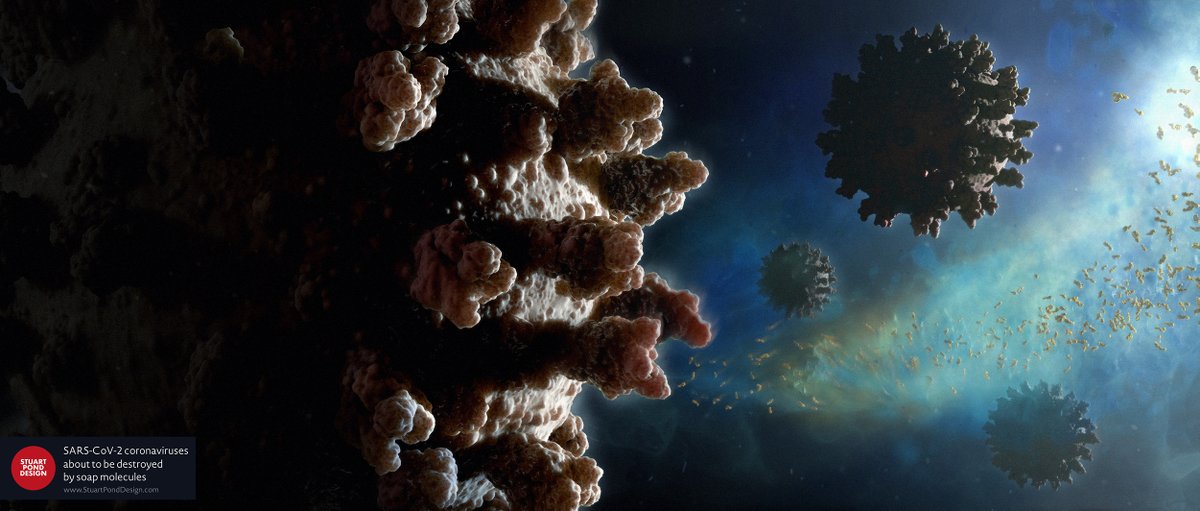

New image created for the day job. SARS-CoV-2 coronaviruses about to be destroyed by soap molecules. Virus models based on structures available at the Protein Data Bank. #ScientificVisualisation

New image created for the day job. SARS-CoV-2 coronaviruses about to be destroyed by soap molecules. Virus models based on structures available at the Protein Data Bank. #ScientificVisualisation